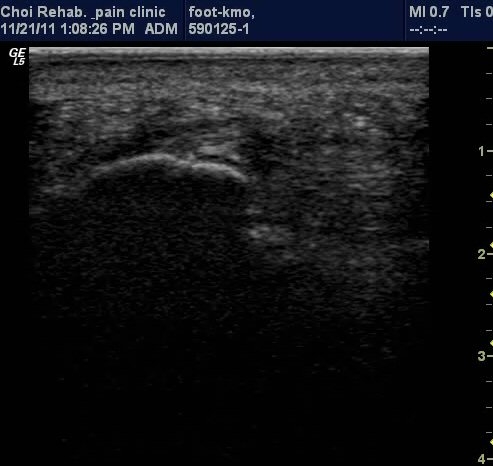

µÚ²ÞÄ¡ Á¾´Ü¸é°Ë»ç¿¡¼­ Á·Àú±Ù¸·ÀÇ Àú¿¡ÄÚ ºÎÁ¾ÀÌ ¶Ñ·ÈÇÔ(±×¸² 1, 2).